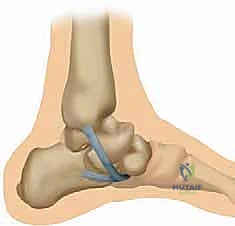

الشكل 1: تشريح مجمع الرباط الزنبركي (منظر ظهري بعد إزالة رأس عظم الكاحل). يوضح هذا المنظر المعقد موقع الأجزاء العلوية الإنسية والسفلية الإنسية. الجزء العلوي الإنسي يقع إنسياً لوتر الظنبوب الخلفي، وينشأ من الجانب العلوي الإنسي للنتوء الداعم لعظم الكاحل والوجه الأمامي لعظم العقب ليلتحم بالعظم الزورقي الإنسي بجوار سطحه المفصلي، مشكلاً دعامة أساسية.

الشكل 2: تشريح مجمع الرباط الزنبركي من المنظر الأخمصي (من أسفل القدم). الجزء السفلي ينشأ من الشق بين الأوجه الأمامية والإنسية لعظم العقب. يلتصق بالسطح السفلي لمنتصف العظم الزورقي، إلى الجانب الوحشي قليلاً من اندغام الجزء العلوي الإنسي من الرباط الزنبركي. هذا الجزء يتحمل الضغط المباشر لوزن الجسم.